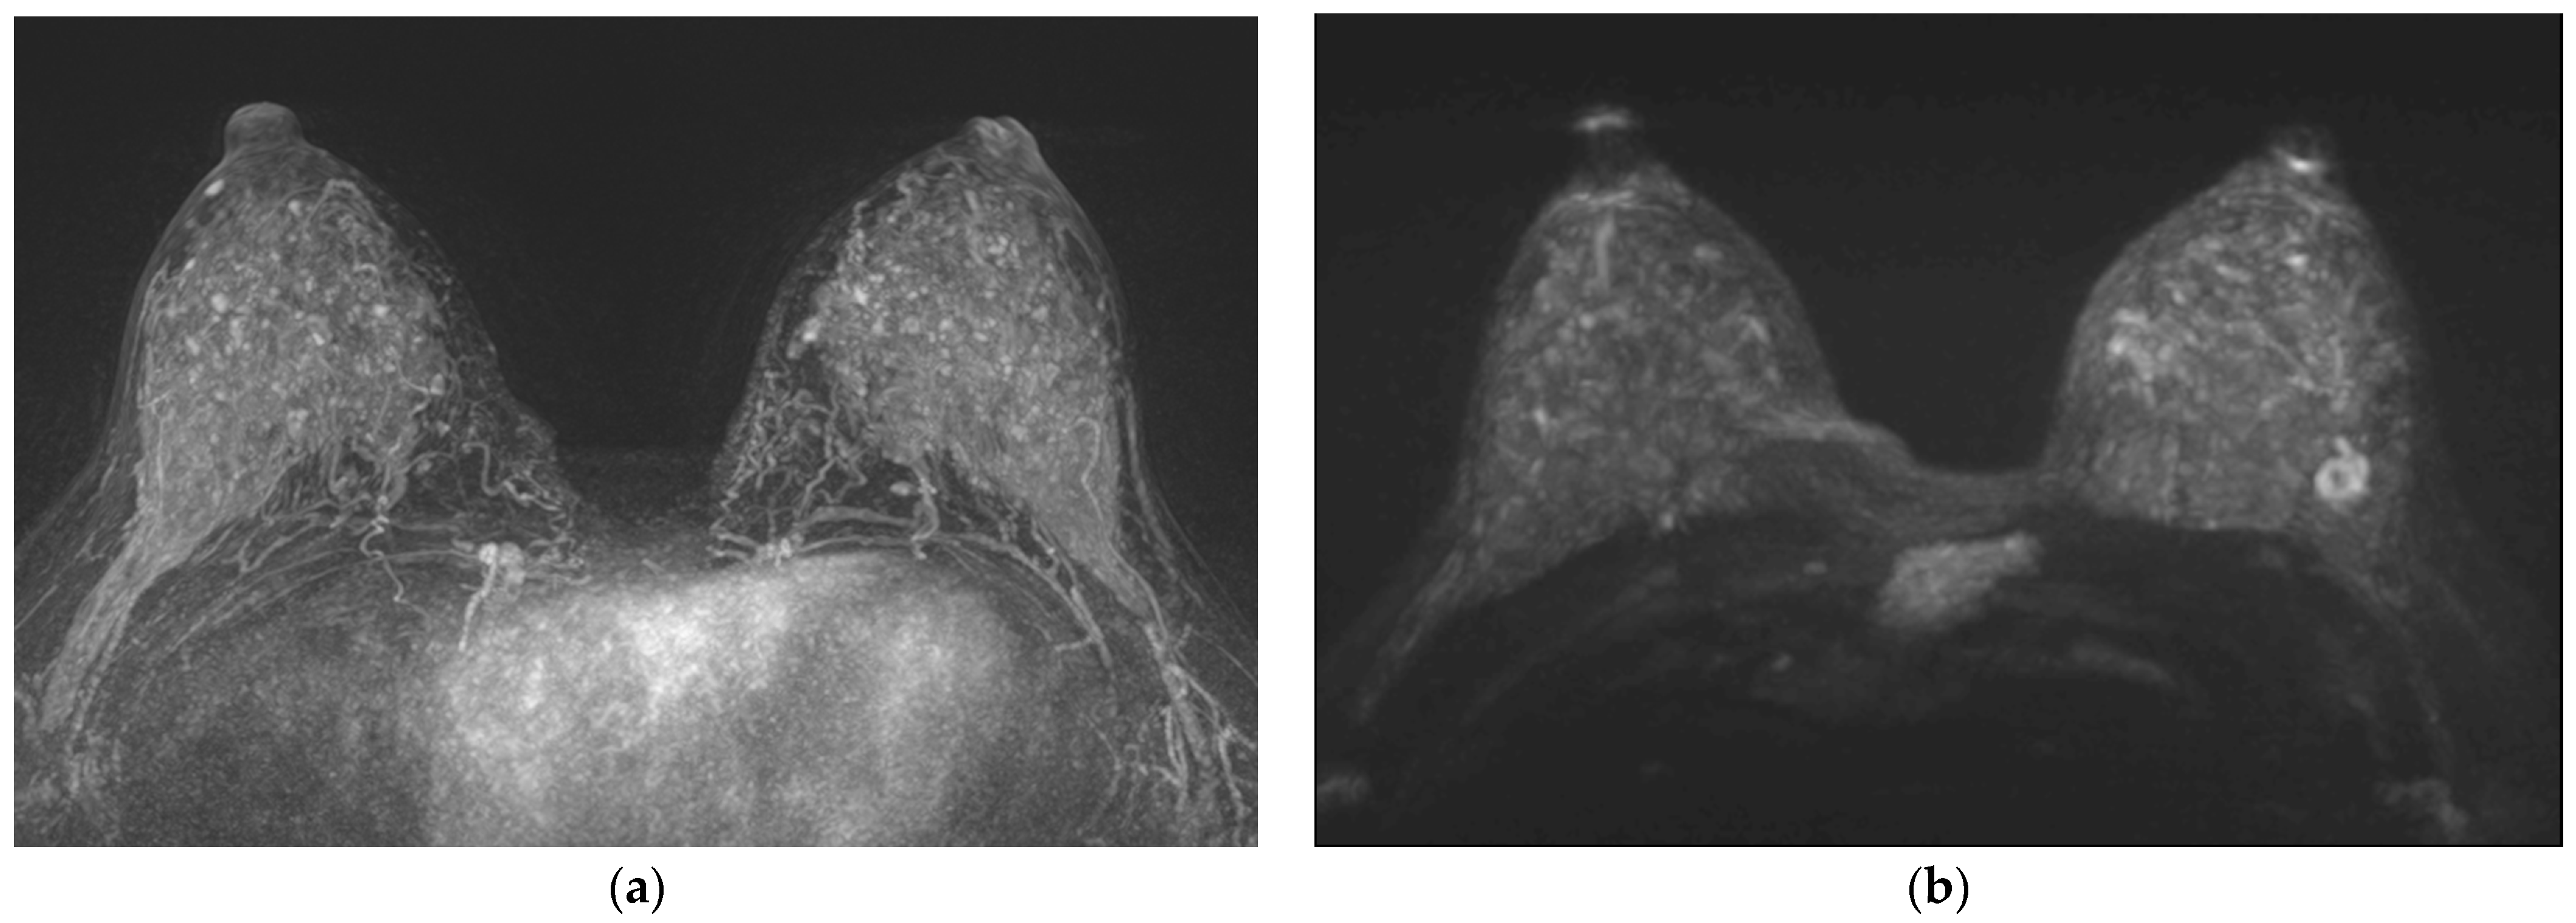

3. Results